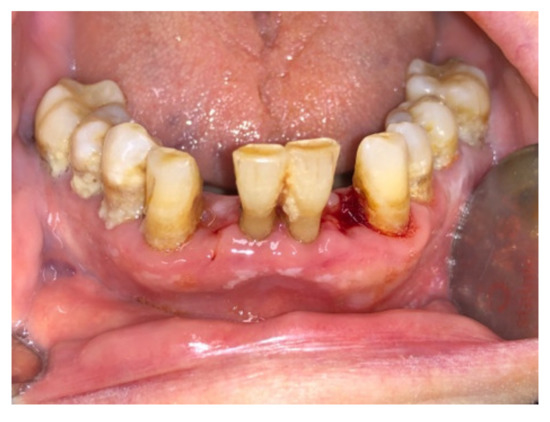

| Tissue colour: | 50% of gingiva red |

| Granulation tissue: | None | |

| Incision margin: | No connective tissue exposed | |

| Suppuration: | None | |

| Tissue colour: | 25% of gingiva red |